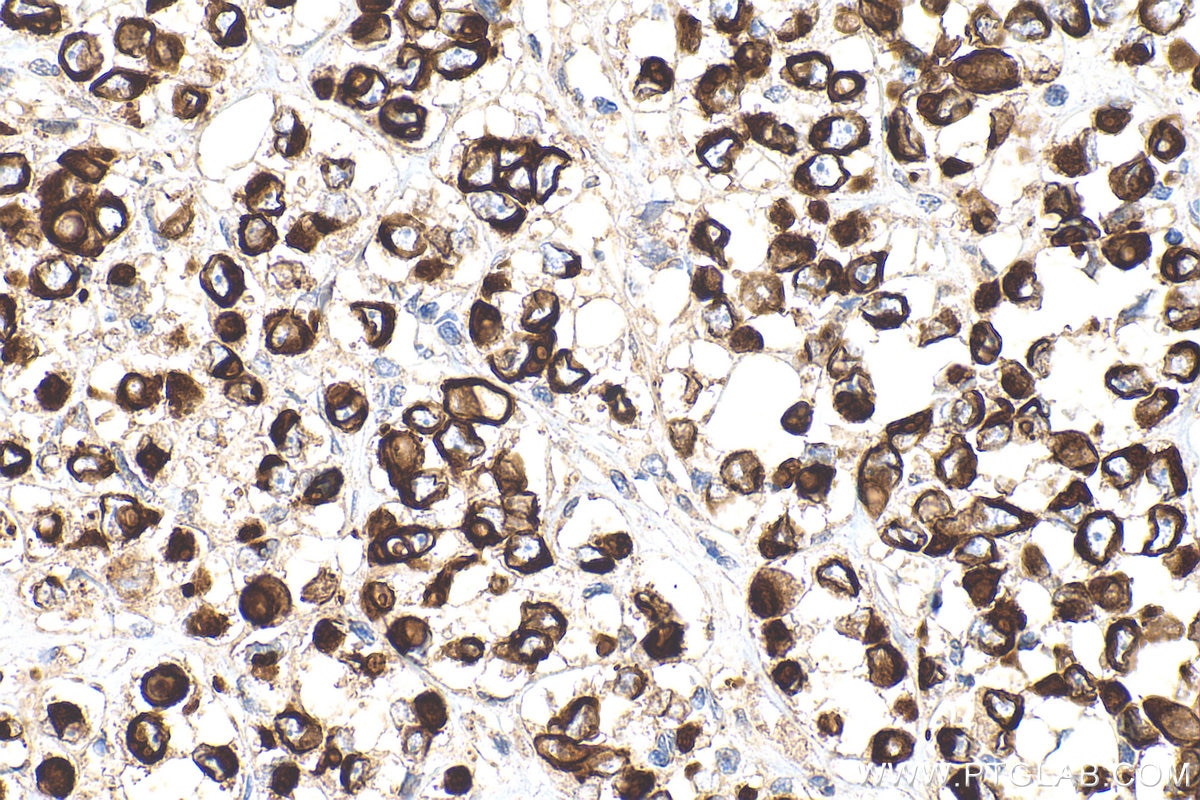

IHC staining of human ovary tumor using 22208-1-AP

Immunohistochemical analysis of paraffin-embedded human ovary tumor tissue slide using 22208-1-AP (Cytokeratin 7 antibody) at dilution of 1:200 (under 40x lens). Heat mediated antigen retrieval with Tris-EDTA buffer (pH 9.0).